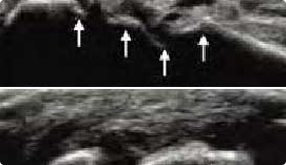

肌骨超声(musculoskeletal ultrasound,MSUS)技术是通过高频超声(3~17Hz)扫描提供优异的临床图像,以清晰显示肌肉等软组织层次关系及其内部机构来诊断肌肉骨骼系统疾病的新型超声检查技术。通过肌骨超声,医生可以分辨毫米级以下动态的这些组织结构肌肉、肌腱、韧带、关节囊、关节面及周围神经等浅表软的毗邻关系、形态大小、结构纹理、血流分布,从而获取这些组织器官的解剖变异、炎症、退行性病以及创伤等病变的全方位信息,从而对疾病进行精准评估。

动态观察滑膜血流信号,早期监测RA活动

清晰显示滑膜异常形态,定量评估RA炎性